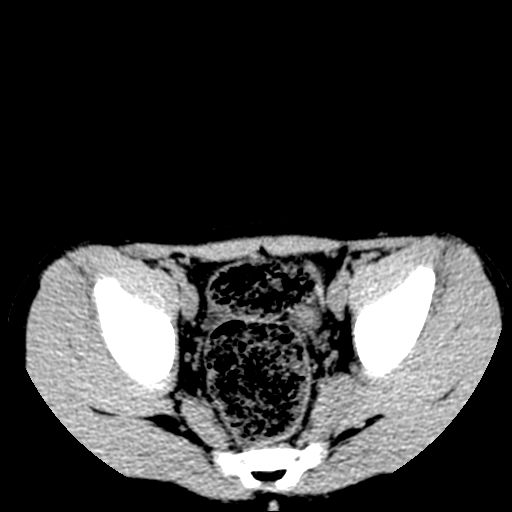

标题: PED3104:男,7岁,反复腹痛3年,再发2天。WBC:10.8X10 9/L,粪 [打印本页]

标题: PED3104:男,7岁,反复腹痛3年,再发2天。WBC:10.8X10 9/L,粪

胸部明显是成年女性,定位象上双侧补过牙齿。轴位像上双侧乳腺退化。可以认定胸部与腹部不是一个人。

腹部好象未见异常。

腹部ct平扫未见明确异常

腹部ct平扫不能提示哪里有病变。